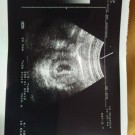

ใช่ค่ะต้องซาวด์ดูค่ะ อันนี้ตอน 10 สัปดาห์ค่ะ

อันนี้ตอน 7w0dคะ